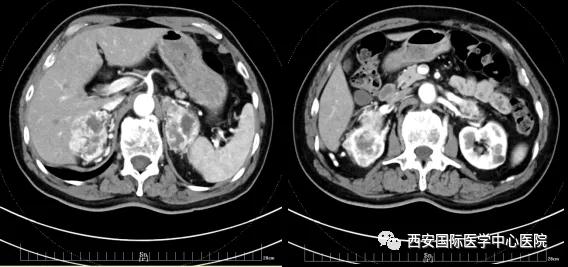

今年七十五歲的患者,來自陜西省商洛市,四月前因腰背部疼痛就診于當(dāng)?shù)蒯t(yī)院,行CT檢查發(fā)現(xiàn)“右腎、雙側(cè)腎上腺占位,前縱膈淋巴結(jié)腫大,雙肺多發(fā)結(jié)節(jié)、胸椎骨質(zhì)破壞,考慮轉(zhuǎn)移瘤”。為進(jìn)一步診斷治療,患者的兒子帶他來到西安某三甲醫(yī)院,查泌尿系CT提示“右腎占位性病變,多考慮腎癌,雙側(cè)腎上腺多發(fā)轉(zhuǎn)移灶,腹膜后多發(fā)腫大淋巴結(jié)”;行穿刺活檢提示“腎透明細(xì)胞癌”;并給予患者口服靶向藥物的治療方案。

自四月份至今,患者一直口服靶向藥物治療(阿昔替尼5mg 2次/日),期間無不良反應(yīng),目前腰背部疼痛癥狀也有所緩解,復(fù)查影像學(xué)資料提示瘤體較前縮小,腫瘤完整切除的可能性明顯提高;而且患者的兒子也是一名外科醫(yī)生,所以他更想為父親完成后續(xù)的手術(shù)治療。

患者一家慕名前來到西安國際醫(yī)學(xué)中心醫(yī)院找到楊增悅教授。楊增悅教授仔細(xì)看完患者的之前的影像學(xué)及病理資料后,診斷為:右腎透明細(xì)胞癌(T4N1M1);并安排他住院。而后,主管醫(yī)生及時(shí)為他完善了術(shù)前檢查及評估。7月15日,在麻醉手術(shù)中心柴偉主任、王彬榮副主任、李娟護(hù)士長、李瑞剛護(hù)士長及全體麻醉手術(shù)中心團(tuán)隊(duì)的有力保障下,成功完成了這臺(tái)“大”手術(shù)。

手術(shù)由楊增悅教授主持,舒濤主治醫(yī)師、王東主治醫(yī)師主刀,黃怡醫(yī)師、王平醫(yī)師協(xié)助完成。由于第四代達(dá)芬奇機(jī)器人更加靈活和精準(zhǔn)的特性,手術(shù)全程順利,尤其是完全精準(zhǔn)的“解鎖”了右腎動(dòng)脈和右腎靜脈的數(shù)十根交互纏繞的分支血管。術(shù)后患者麻醉恢復(fù)后生命體征平穩(wěn),順利返回泌尿外科普通病區(qū)進(jìn)一步康復(fù)。